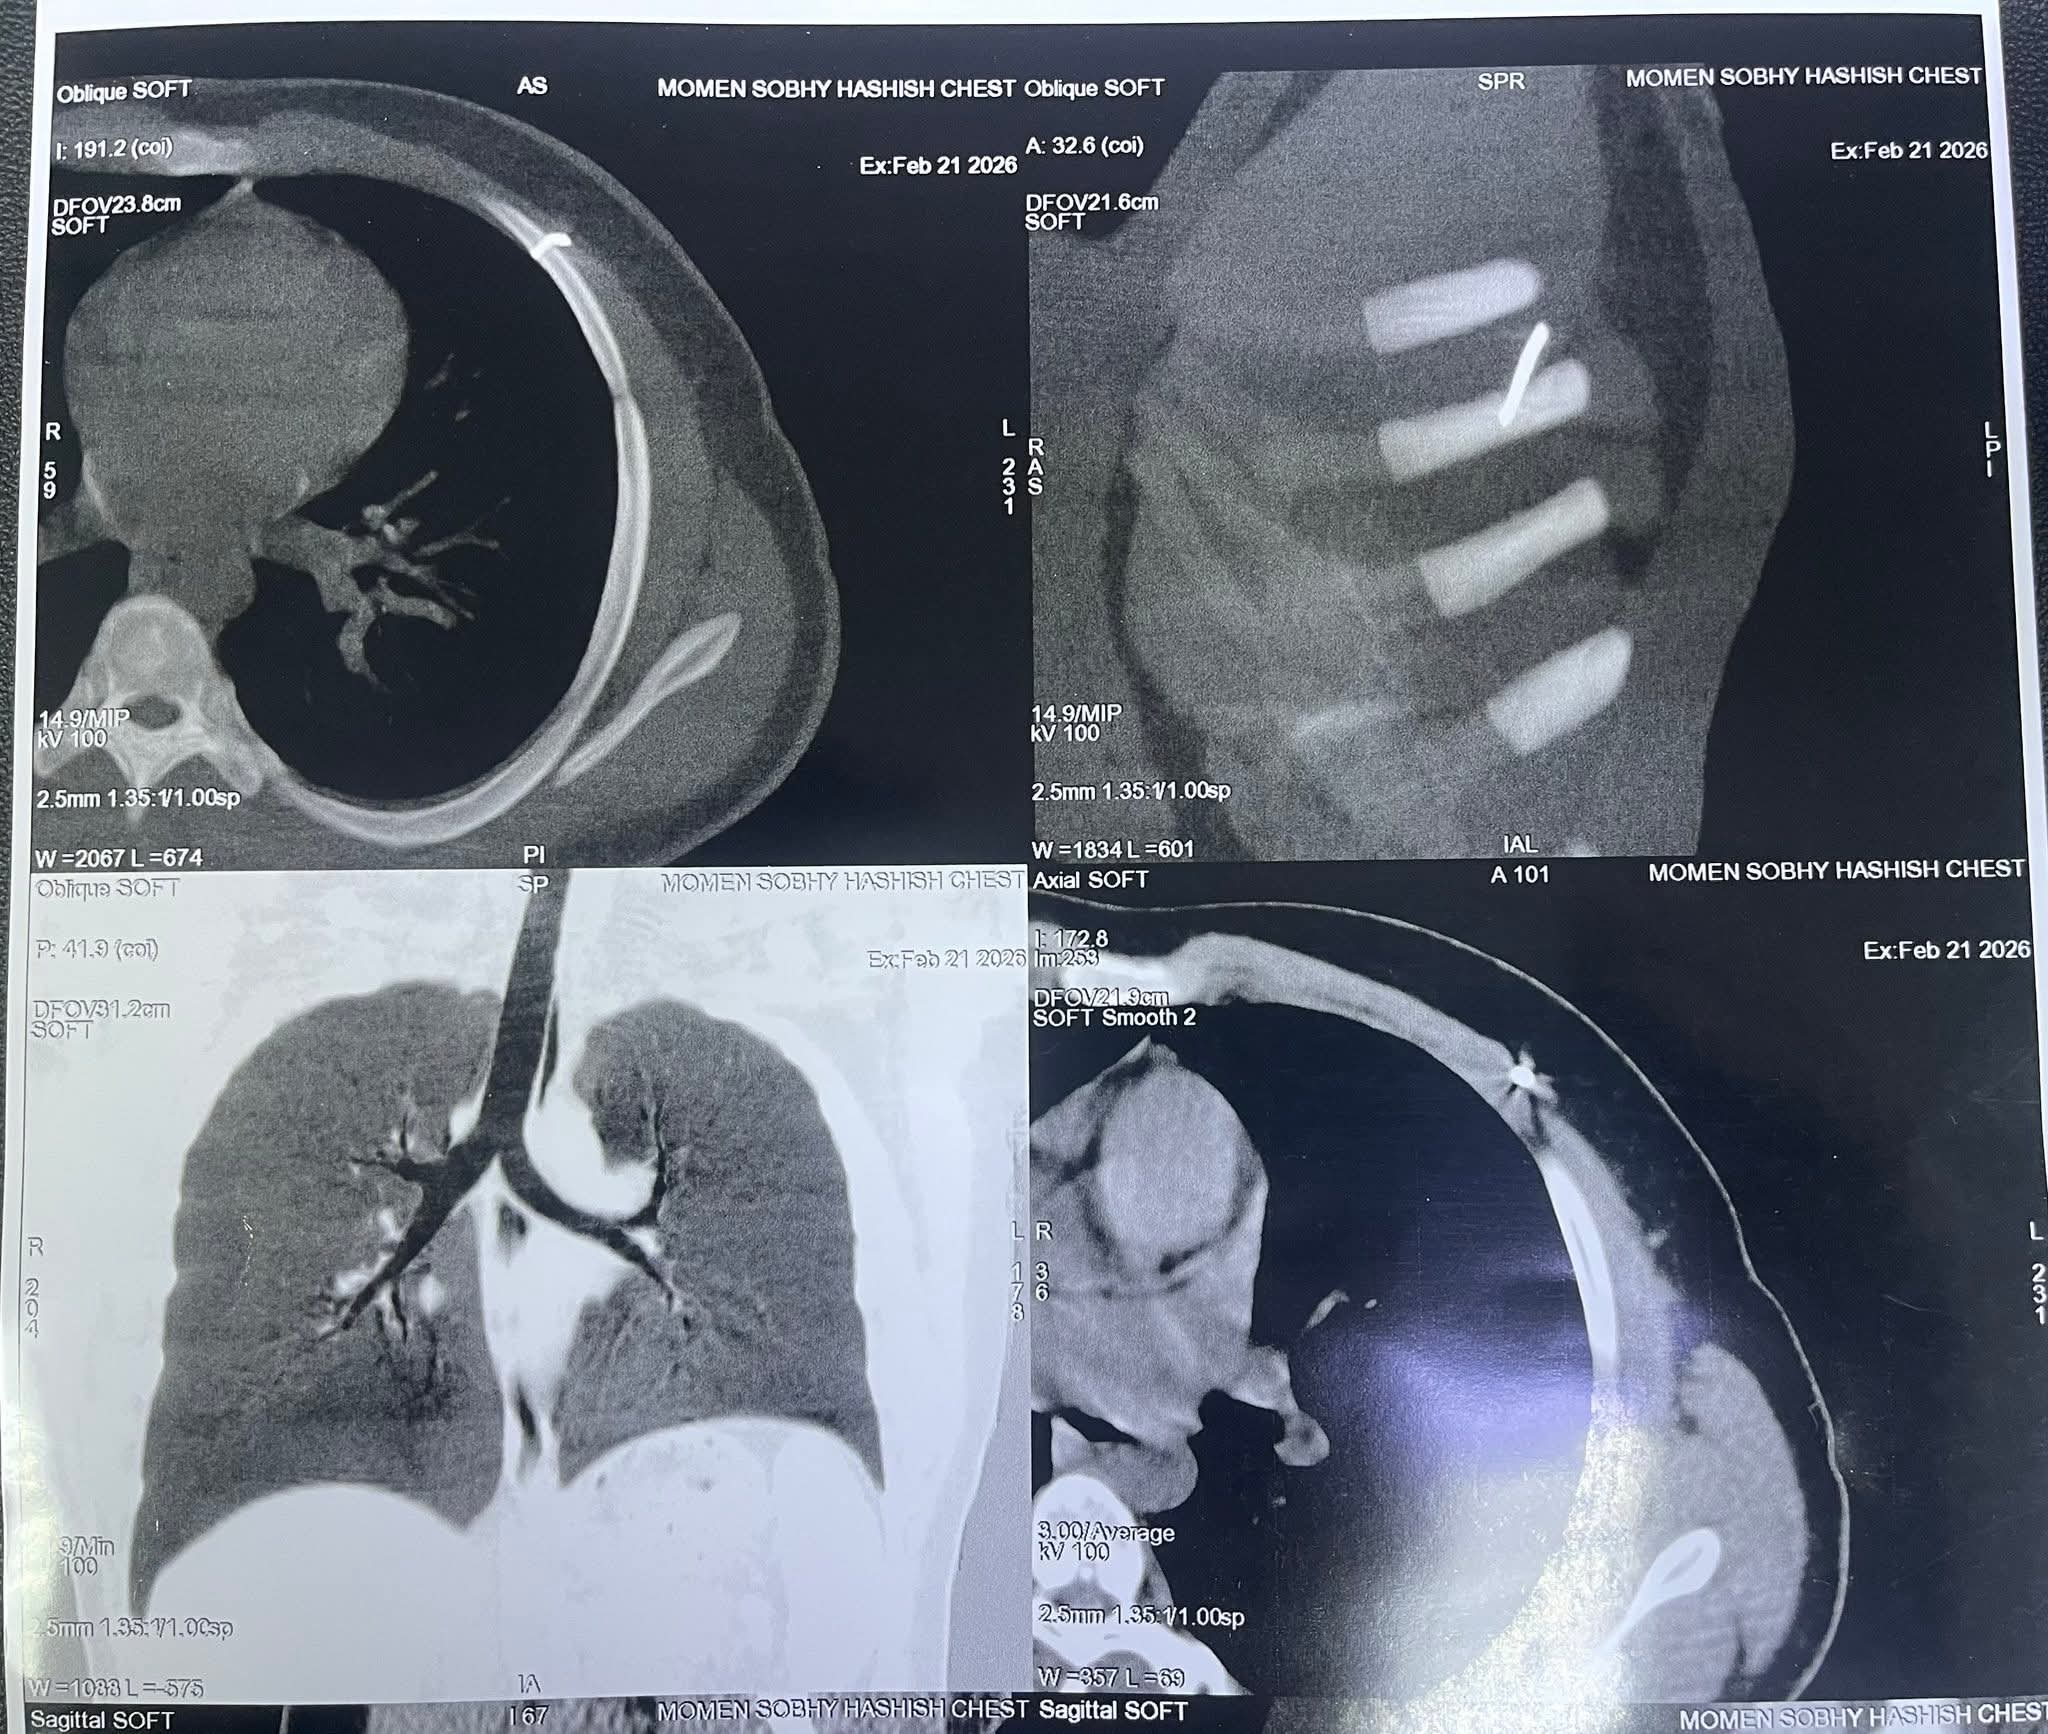

وأضاف أنه بعد إجراء الإشاعات اللازمة تبين استقرار المسمار في أحد الضلوع وحدوث اعوجاج بالمسمار ليستقر بالضلع الخامس الجانب الأيسر من الصدر.

الأشعة توضح مكان المسمار